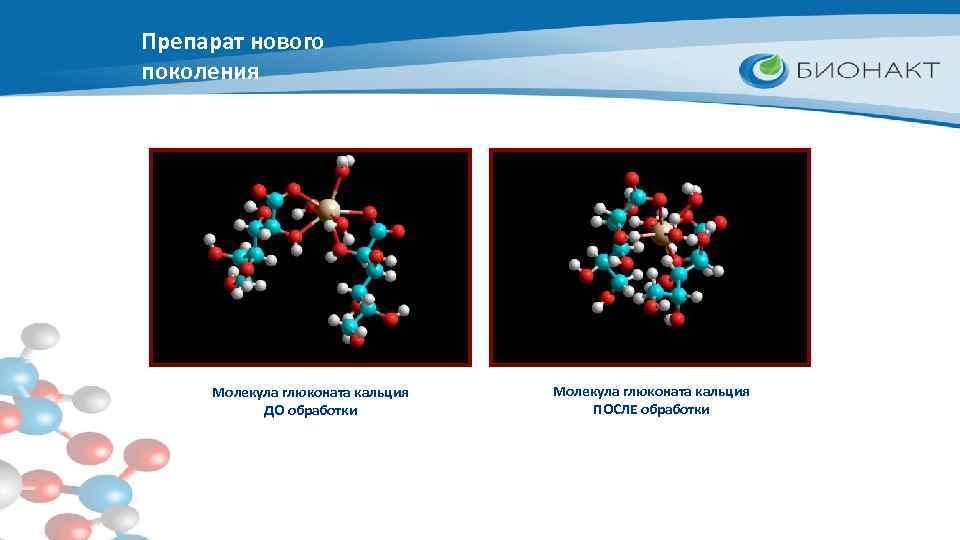

Препарат нового поколения Уникальная форма молекулы препарата увеличивает проницаемость мембраны клеток для микроэлементов, обеспечивая эффективное усвоение не только кальция, но и других микроэлементов, таких как железо, магний, калий, фосфор. В результате возрастает выносливость организма в целом. Молекула глюконата кальция ДО обработки Молекула глюконата кальция ПОСЛЕ обработки

Препарат нового поколения Молекула глюконата кальция ДО обработки Молекула глюконата кальция ПОСЛЕ обработки